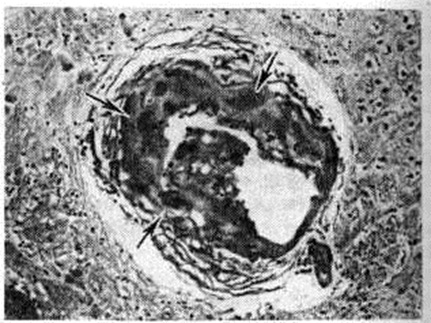

Геморрагический инсульт, как правило, возникает при заболеваниях, протекающих с повышенным артериальное давление. Это обусловлено тем, что сосудистые кризы (смотри полный свод знаний), характерные для гипертонической болезни (смотри полный свод знаний) и артериальной гипертензии (смотри полный свод знаний Гипертензия артериальная), приводят к морфологический изменениям стенок внутримозговых сосудов с нарушением их проницаемости — плазматическому пропитыванию (рисунок 1), некрозам (рисунок 2), образованию микроаневризм (рисунок 3) и их разрывам. Разрыв врождённых артериальных и артериовенозных аневризм может протекать на фоне нормального давления. Преимущественная локализация и характер геморрагий определяются особенностями ангиоархитектоники различных отделов мозга. При гипертонической болезни наиболее тяжёлым изменениям подвергаются сосуды подкорковых узлов и зрительного бугра. Это объясняется отхождением глубоких ветвей под прямым углом от средней мозговой артерии, являющейся продолжением внутренней сонной артерии, и незначительным числом анастомозов сосудов в этой области. В связи с этим на вскрытии кровоизлияния наиболее часто (40%) обнаруживаются в подкорковых узлах с распространением в прилежащее белое вещество (так называемый латеральные кровоизлияния, то есть расположенные латерально от внутренней капсулы, рисунок 4). Второе место по частоте (16%) занимают обширные кровоизлияния, разрушающие подкорковые узлы, внутреннюю капсулу, зрительный бугор (так называемый смешанные кровоизлияния — рисунок 5). Кровоизлияния в зрительный бугор (так называемый медиальные — рисунок 6) составляют 10%, в мозжечок — 6—10%, в мост мозга — 5% от общего числа внутримозговых геморрагий. Кровоизлияния только в белое вещество полушарий мозга встречаются крайне редко. Подразделение полушарных кровоизлияний на латеральные, медиальные и смешанные имеет особое значение в связи с хирургическим лечением геморрагического Инсульт.

Кровоизлияния типа гематомы сопровождаются образованием полости, содержащей жидкую кровь или свёртки крови; они составляют 85% внутримозговых кровоизлияний, наиболее часто развиваются в подкорковых узлах, реже в мозжечке. Основной механизм развития гематомы — разрыв патологически изменённого сосуда (рисунок 7). Формирование гематомы идёт путём раздвигания кровью вещества мозга с перемещением его участков, что возможно благодаря резервным пространствам (желудочки, подпаутинное пространство). Размеры гематомы при этом превышают объем разрушенного кровью вещества, сдавление окружающих отделов незначительно; лишь при кровоизлиянии в мозжечок сдавление вещества мозга весьма существенно в связи с анатомическими особенностями задней черепной ямки (рисунок 8).